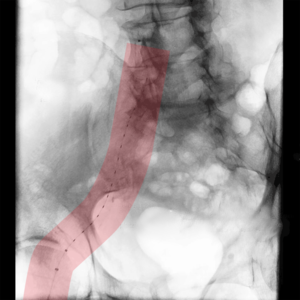

Für interventionelle Behandlungsmethoden ist ein Zugang ins Gefäßsystem notwendig. Dieser wird am häufigsten in der Oberschenkelarterie/-vene im Bereich der Leiste oder der Armarterie/-vene im Ellenbogen- oder Handgelenksbereich angelegt.

Dazu erfolgt nach gründlicher Desinfektion und lokaler Schmerzstillung die Nadelpunktion des Gefäßes mit anschließender Einführung einer Gefäßschleuse (Gefäßventil), die dem Behandler ermöglicht, unterschiedliche Kathetersysteme zur Behandlung ohne Blutungs- und Verletzungsgefahr schmerzarm in die zu behandelnde Gefäßregion einzuführen.

Nach der Behandlung wird der Gefäßzugang/Punktionsstelle wieder mit einem Verschlusssystem abgedichtet und ein Kompressionsverband von außen angelegt, damit es zu keiner unkontrollierten Blutung kommt. Zur Sicherheit ist eine mehrstündige Bettruhe einzuhalten.